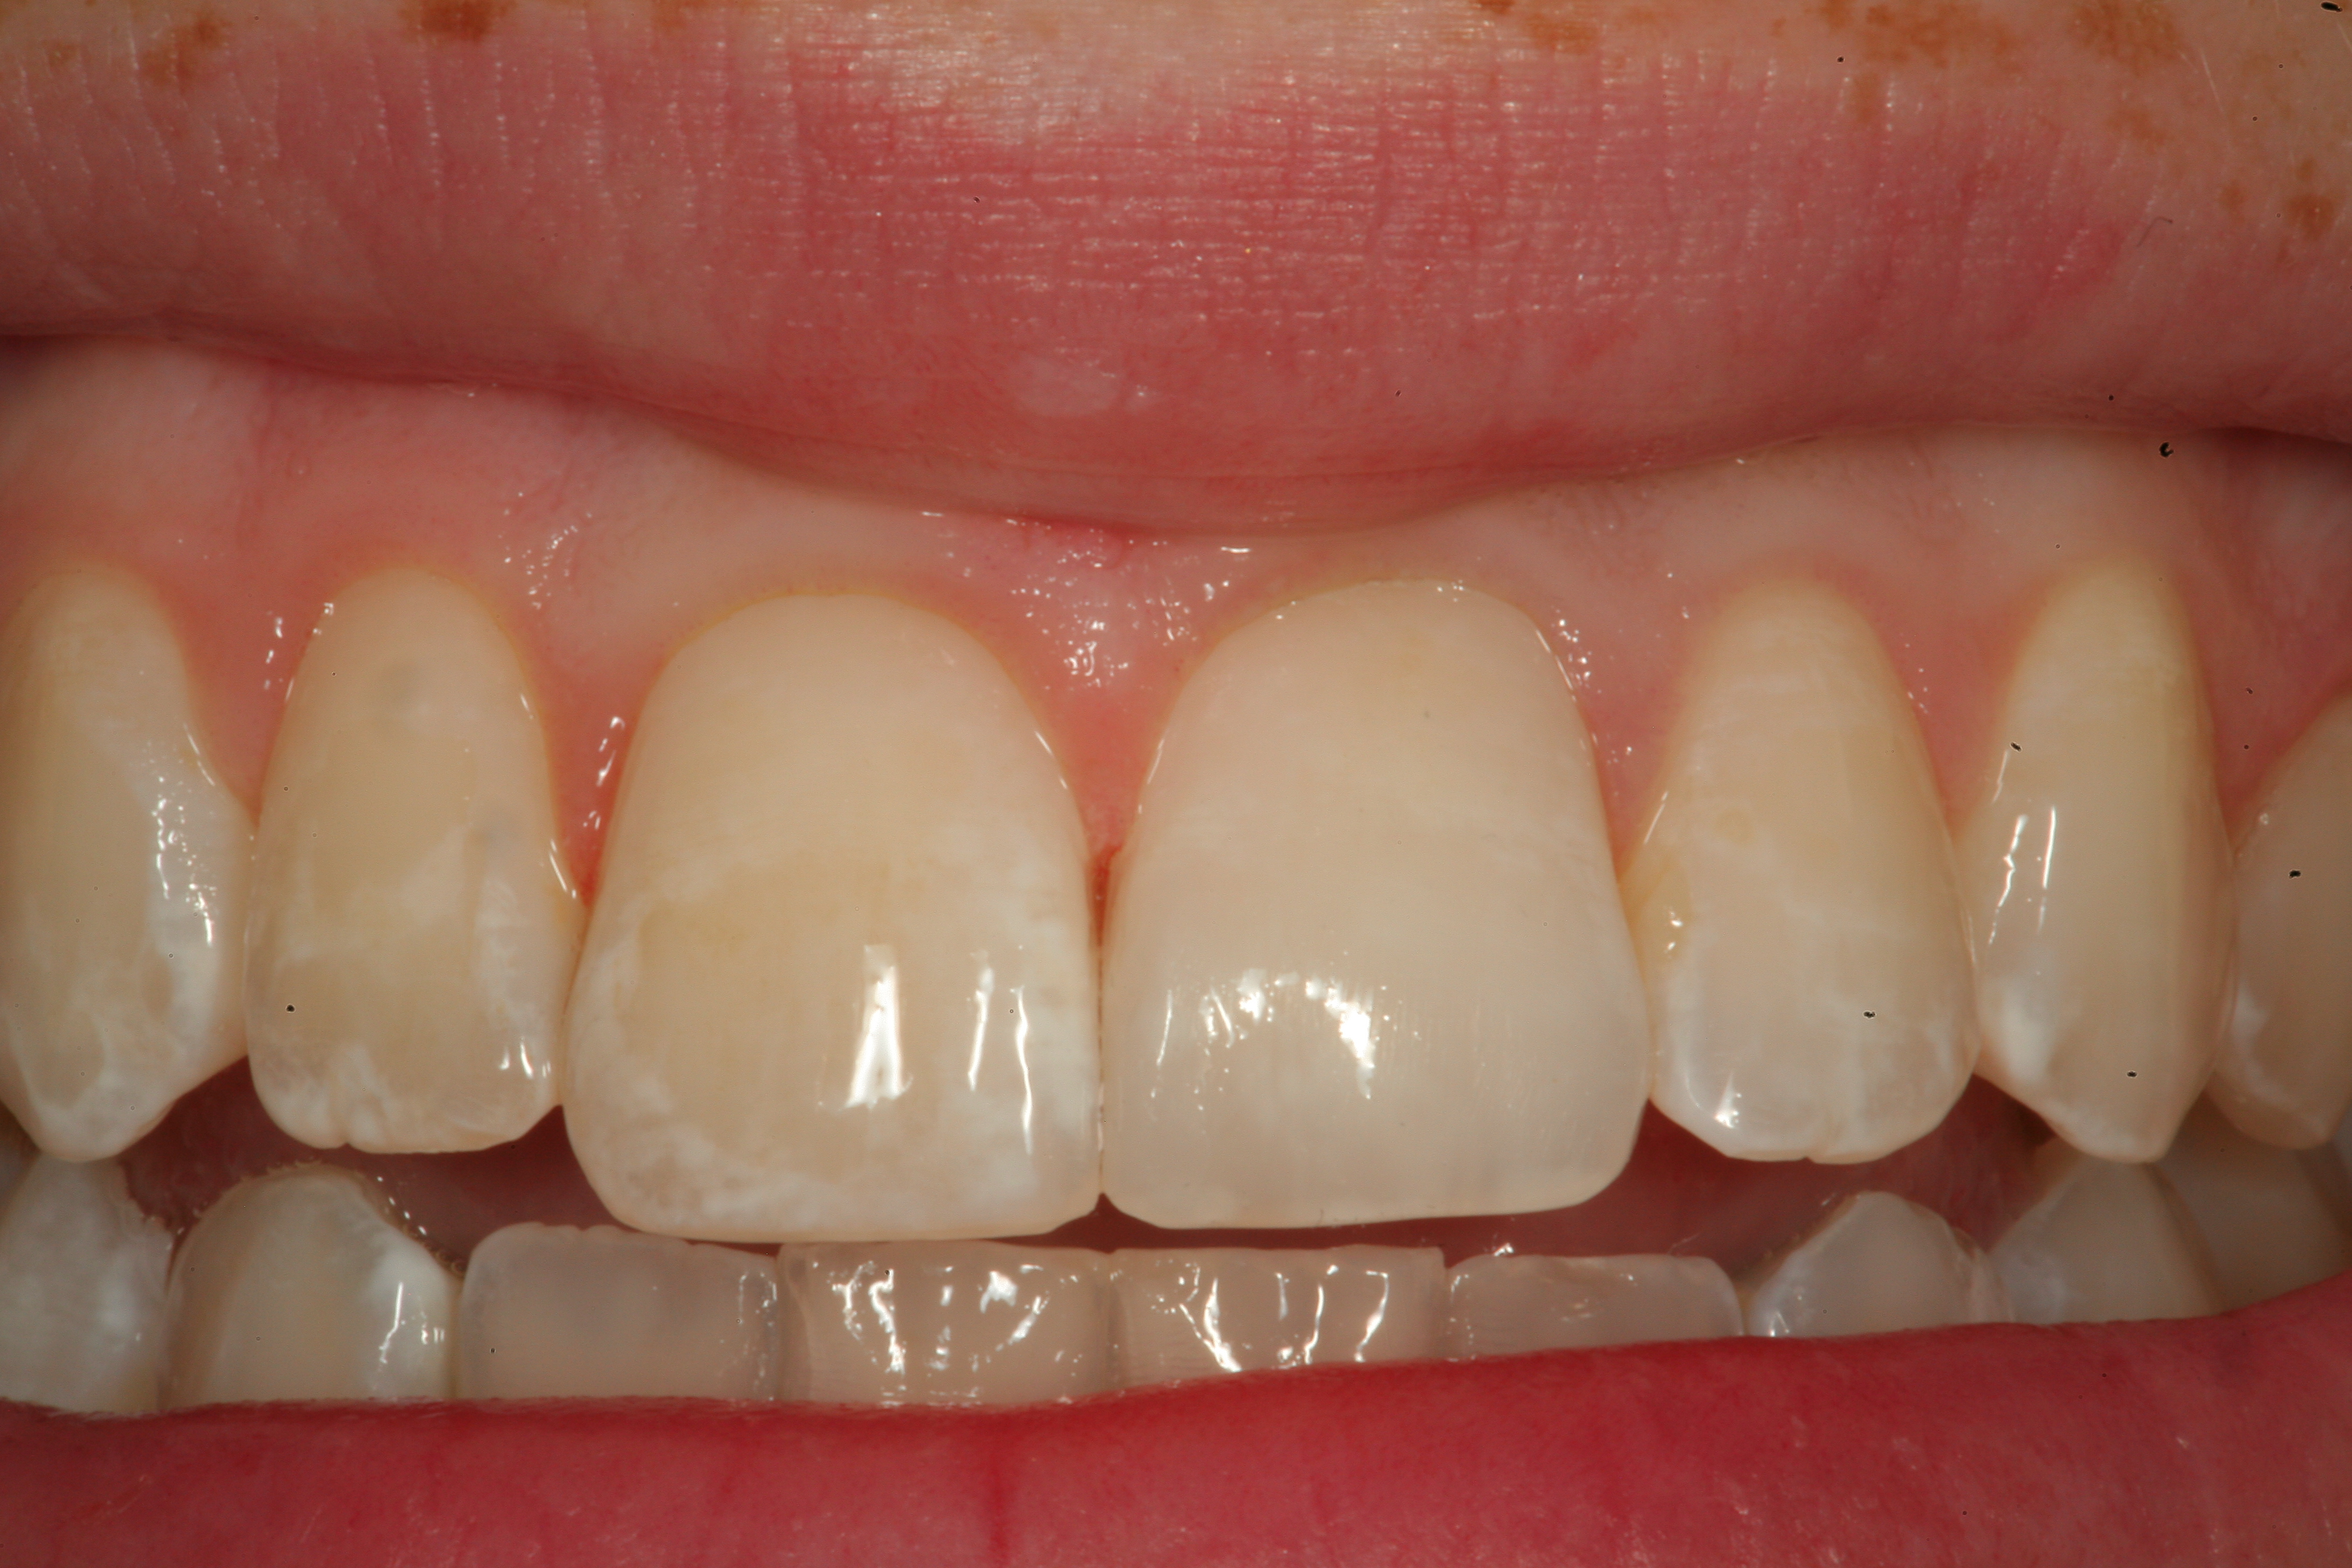

Fig 12. A Class IV mesial incisal fracture is shown from the facial aspect on tooth No. 9.

Figure 12

Fig 19. The completed Class IV Giomer restoration is seen on tooth No. 9 from the facial aspect. Note the esthetic quality of this layered anterior composite restoration as it compares with the surrounding natural teeth.

Figure 19